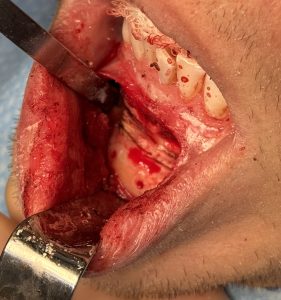

Case Study

Osteotomy Strategy

A. Re-osteotomy considerations

- Expect dense scar tissue and altered landmarks

- Osteotomy often must be slightly higher or lower than original cut

- Maintain ?5 mm clearance from mental foramen

- Use guarded saw + osteotomes to protect nerve

B. Segment control

- Mobilize fully — partial mobilization leads to relapse

- Release inferior border scar bands if vertical change planned

- Check passive seating before fixation